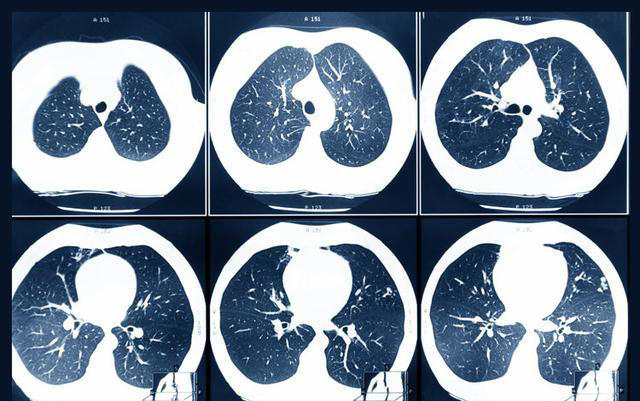

第二天就请假去了医院检查,结果发现结节已经增长到了14 mm,且出现了实性成分。后续的增强CT、肿瘤标志物检查高度怀疑是恶性肿瘤,刘先生被安排入院进行相关治疗。好在刘先生的病程还处于早期,可以进行手术治疗,术后他很快就康复出院了。

很多患者在罹患肺结节后,身体没有任何不适症状,这种情况下只能通过胸部CT检查来发现结节。

当胸部CT检查普遍后,很多人会被检查结果上的肺结节结果吓到,担心结节会发生癌变。在我国第31个全国肿瘤防治宣传周上,中国抗癌协会整合肿瘤分会青委会主委薛建新明确指出,体检中查出的肺结节95%为良性,只有5%有恶变的可能性。

? 长相:结节有毛刺征、分叶状、血管集束征、胸膜凹陷征等特征,恶性程度较高

? 变化:在发现结节后,医生会建议定期进行复查,复查过程中发现结节变大或是形态发生了改变,都要警惕可能是恶变了

? 密度:从危险程度上来看,是混合型>磨玻璃>实性